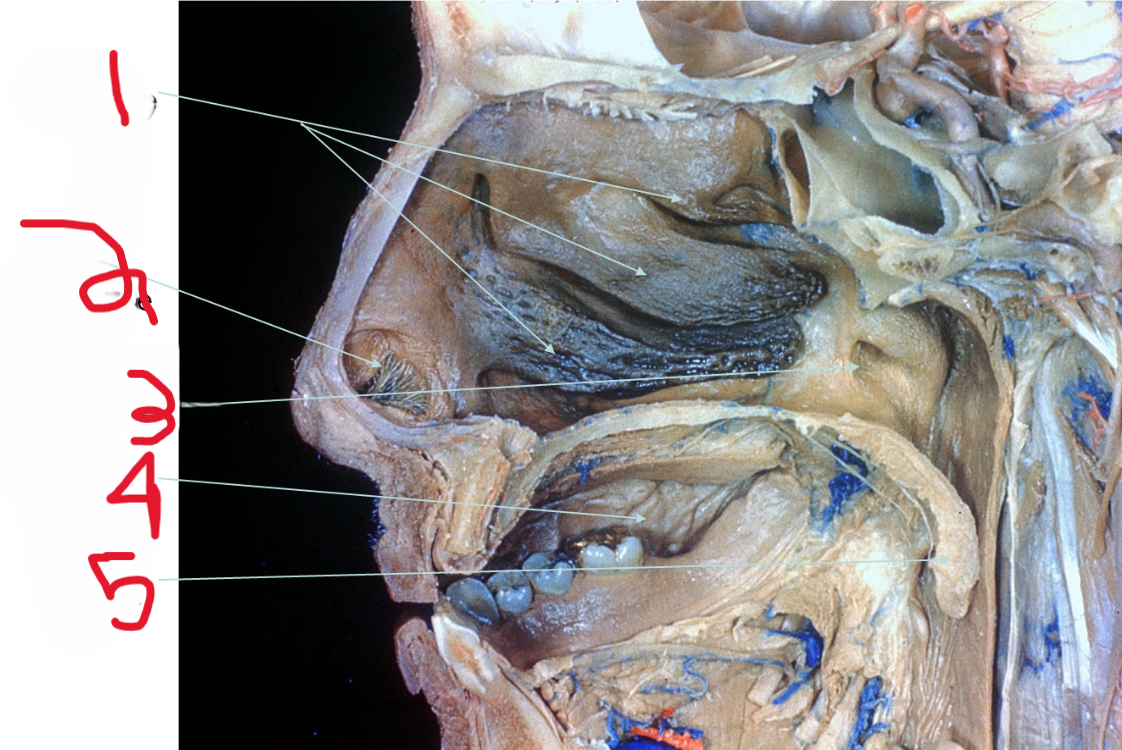

Nasal Conchae

What is depicted by #1

Nasal vestibule

What is depicted by #2

Opening of Pharyngotympanic (auditory) tube

What is depicted by #3

Oral cavity

What is depicted by #4

Uvala

What is depicted by #5